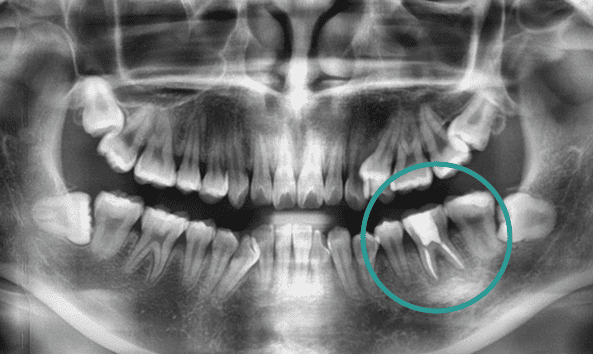

골치 아픈 사랑니, 대학병원 가지 않으셔도 됩니다.

사랑니는 기형적으로 맹출되거나

잇몸 속에 매복되는 경우가 많아 발치가 까다로울 수 있습니다.

특히, 인접 치아를 손상시키지 않고 신경을 보호하며 발치하려면

전문적인 노하우가 필수입니다. 그래서 사랑니 발치는 많은 고민과 망설임을 동반하는

어려운 선택이 될 수 있습니다. 올디플란트치과는 이런 걱정을 덜어드릴 자신이 있습니다.

사랑니 발치를 위해 치과를 찾아 헤매고 계신가요?

매복 사랑니는 신경과 가까워 발치 시

신경 손상의 위험이 높아

일부 동네 치과에서는 치료를 권하지 않기도 합니다.

하지만 올디플란트치과는

대학병원 가기 전에 방문하는 치과로 유명하며,

타원에서 발치하지 못한 케이스도

책임지고 해결해드리고 있습니다.